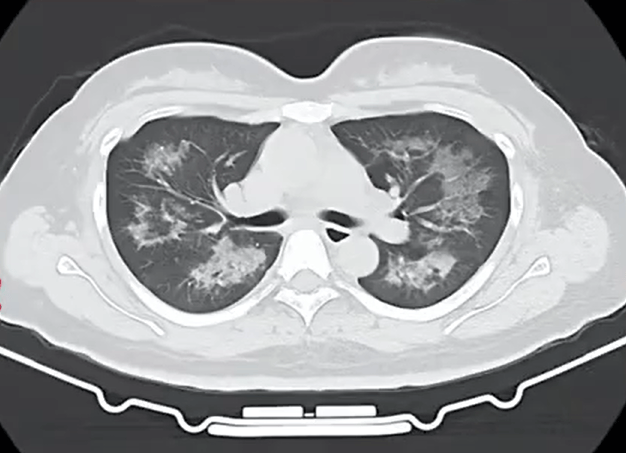

胸部CT进一步显示

她的双肺出现多发斑片状模糊影,被诊断为间质性肺炎。